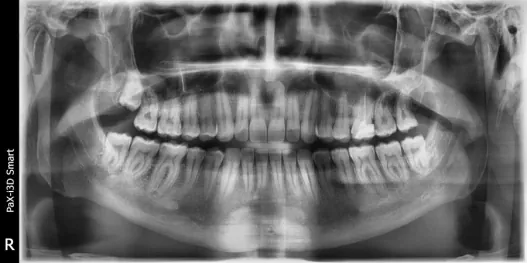

Намерете идеи за вдъхновение за Кариес и профилактика

Галерия с впечатляващи идеи за Кариес и профилактика създадени от нашите експерти. Намерете перфектната идея за Кариес и профилактика и направете своята резервация незабавно.